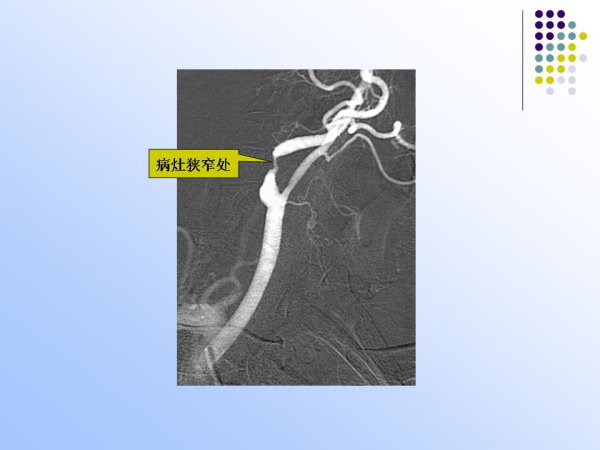

【治疗脑血管病的新技术:血管内介入治疗】—神经内科脑卒中筛查与防治办公室

神经内科

脑卒中筛查与防治办公室